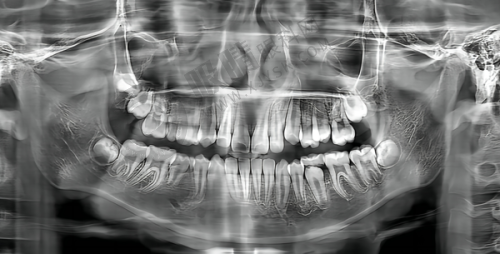

精良的设备是保护口腔治疗成效的重要因素,沈阳米兰口腔门诊部(奥莱店)配备了国内外精良的口腔诊疗设备。

德国西诺德CAD/CAM3D齿雕系统:这一精良技术的应用,使得牙齿修复更加精细、效率高。它可以快速制作出与患者口腔理想匹配的牙齿修复体,大大缩短了治疗时间,提高了患者的舒适度。

牙齿种植中 心:这里是沈阳口腔种植专职的演示中 心及培训基地,种植系统选择性多。精良的设备和多样化的种植系统,能够满足不同患者的需求,为牙齿缺失的患者提供更优质的种植解决方案。